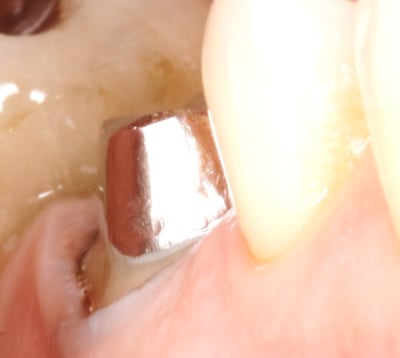

ce matin , je viens de finaliser 1 ccc .

taille profonde sur une fracture vestibulaire . il a fallu prendre l empreinte au fil , avec des limites vest profondes . là si j avais fait un prov , j aurais eu une rétraction le jour du scellement , et à coup sur perdu de la gencive attachée , donc pas de prov .

pourtant ç est une coquette :-)) , ben non , faut ce qu'il faut . elle n a eu le choix que de sa couleur : " bien bien blanc , voyez docteur "

photo de l empreinte la semaine passée , et avant scellement aujourd’hui , et couronne ccc scellée .